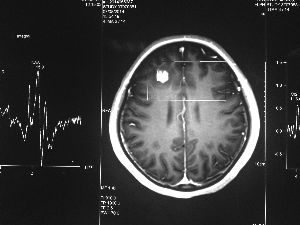

方框亮點(diǎn)為CT片顯示的異物

今年6月份,張敏在宿舍休息時(shí),又發(fā)起了癲癇,也是口吐白沫,渾身抽搐。送到蘇州一家大醫(yī)院,頭顱核磁共振檢查出,張敏大腦右額葉處有一處病灶,也就是大腦額頭處有個(gè)東西。

腦袋里的東西,到底是腫瘤還是其他什么東西,這個(gè)謎像個(gè)石頭一樣,壓得張敏一家人喘不過(guò)氣。7月份,張敏一家又來(lái)到南京腦科醫(yī)院求醫(yī),第三次檢查后,醫(yī)生覺得很像是寄生蟲。不過(guò),影像的檢查,只能作為醫(yī)生推測(cè)的依據(jù),具體是什么,只有手術(shù)拿出來(lái)后才能知道。